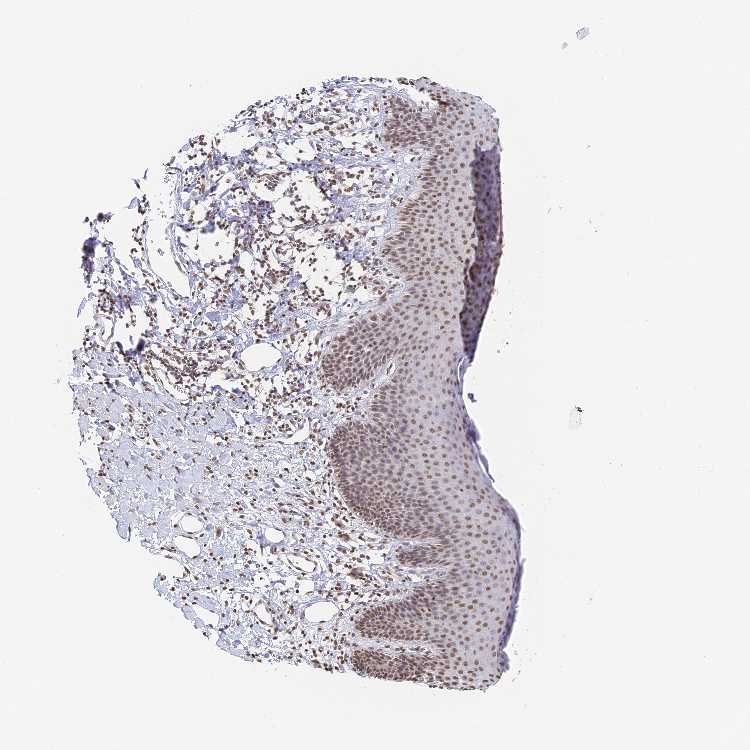

SKIN 2 - Antibody stainingi

Antibody staining in the annotated cell types in the current human tissue is reported as not detected, low, medium, or high, based on conventional immunohistochemistry profiling in selected tissues. This score is based on the combination of the staining intensity and fraction of stained cells.

Each image is clickable and will lead to virtual microscopy that enables deeper exploration of all samples and also displays staining intensity scores, fraction scores and subcellular localization as well as patient and tissue information for each sample.

Antibody HPA045657

Epidermal cells Medium